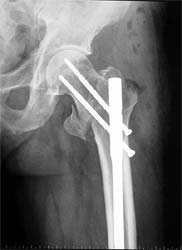

股骨粗隆间骨折,严重移位。            采用闭合复位伽马钉内固定。